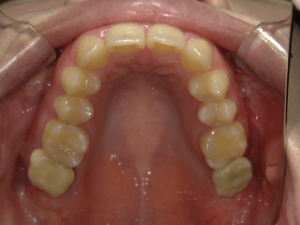

30代 女性 インプラント治療(鎮静療法)

| 主訴 | 口腔内かなり状態悪く、これから先しっかり噛んで食事ができるようにインプラントを入れたい。 |

| 部位 | 左上3,5,7、右下5 |

| 治療期間 | 約11ヶ月 |

| 費用 | ¥2,145,000(税込) |